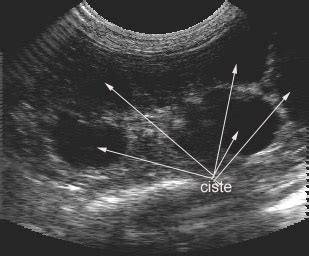

Urin odteka iz ledvic po sečevodih v mehur, ki se lahko raztegne ali skrči. Na mestih, kjer sečevoda vstopata v mehur, sta enosmerni zaklopki. Ti preprečujeta, da bi urin tekel nazaj proti ledvicam. Včasih ti zaklopki ne delujeta dobro, zato med uriniranjem, ko se poveča tlak v mehurju, urin zateka nazaj proti ledvicam, kar imenujemo refluks. Vnetje sečil je dokaj pogosta bolezen otrok z motnjami v razvoju sečil. Ker vsako vnetje ledvic pusti brazgotino in delno okvari delovanje ledvic, je treba čim prej izključiti takšno motnjo. Pogosto gre za oviro pri odtoku seča ali za moteno delovanje zaklopk pred vstopom sečevodov v mehur ali na izhodu sečnice iz mehurja. Te motnje se da lepo prikazati s slikanjem sečnih poti - ultrazvočno slikanje, rentgensko slikanje s kontrastom ali z vbrizganjem radioizotopa. Vsako je prilagojeno starosti otroka in pričakovani motnji oziroma bolezni. Z ultrazvokom lahko najdejo različne razvojne nepravilnosti, kot na primer razširjen votli sistem ene ali obeh ledvic že pri novorojenčku. Med votli sistem štejemo ledvični meh (pielon), ki se nadaljuje v sečevod (ureter). Pri nekaterih dojenčkih je ta sistem lahko razširjen, ponavadi zaradi motnje v odtoku seča. Praviloma je razširjen del nad oviro ali zaporo. Tovrstne napake se da dobro odkrivati z ultrazvokom, ki je enostavna, hitra in neškodljiva preiskava.